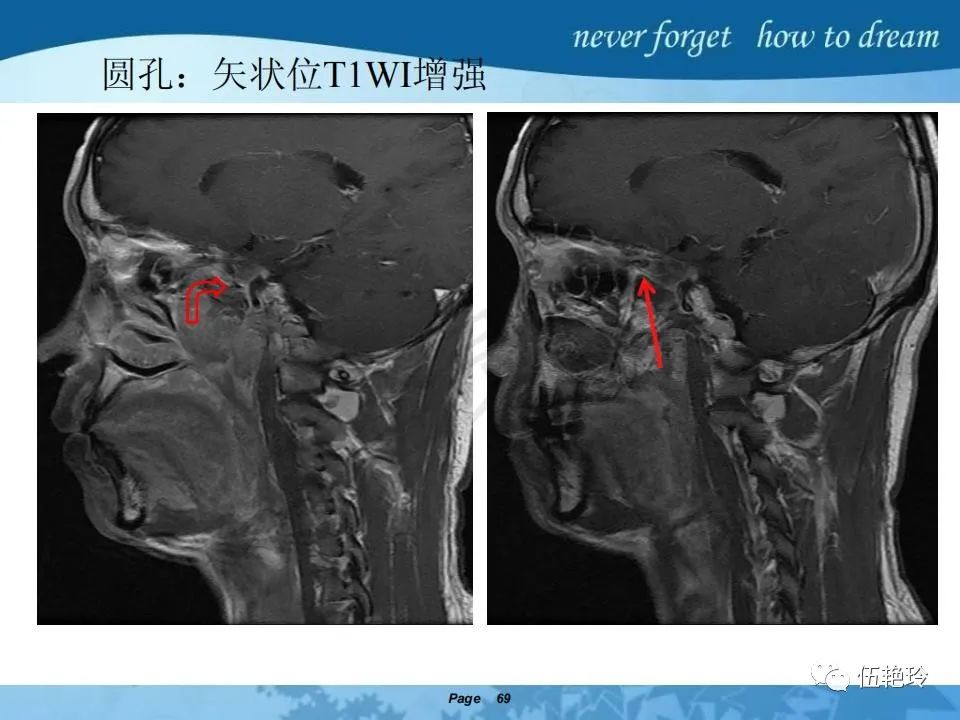

2.2 鼻咽特有的解剖途径:鼻咽癌原发灶循序进展的总途径:鼻腔(47.8%)→翼腭窝(15.2%)→ 眶下裂(3.2%)→眶尖(1.2%)→海绵窦(0.6%)。

2.31 向上颅内:①鼻咽顶壁→破裂孔(岩尖、斜坡)→蝶窦、海绵窦;②鼻咽顶壁→蝶骨基底部→蝶窦、海绵窦;③鼻咽侧壁→茎突前间隙→蝶骨大翼(卵圆孔)→海绵窦;④鼻咽侧壁→茎突前间隙→翼腭窝→ 颞下窝;⑤鼻咽前壁→鼻腔→翼突、翼腭窝→眶下裂→眶尖→海绵窦;⑥鼻咽前壁→鼻腔→上颌窦、筛窦;